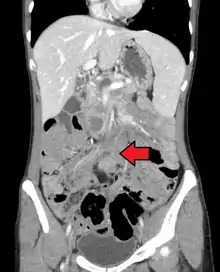

| Desmoid tumor as seen on CT scan | |

MRI or CT imaging scans are commonly used for monitoring.[45][1]